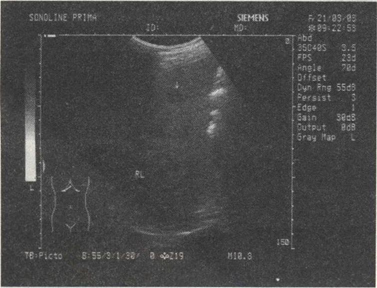

32.男,49岁,肥胖,血脂增高。结合超声声像图诊断为()